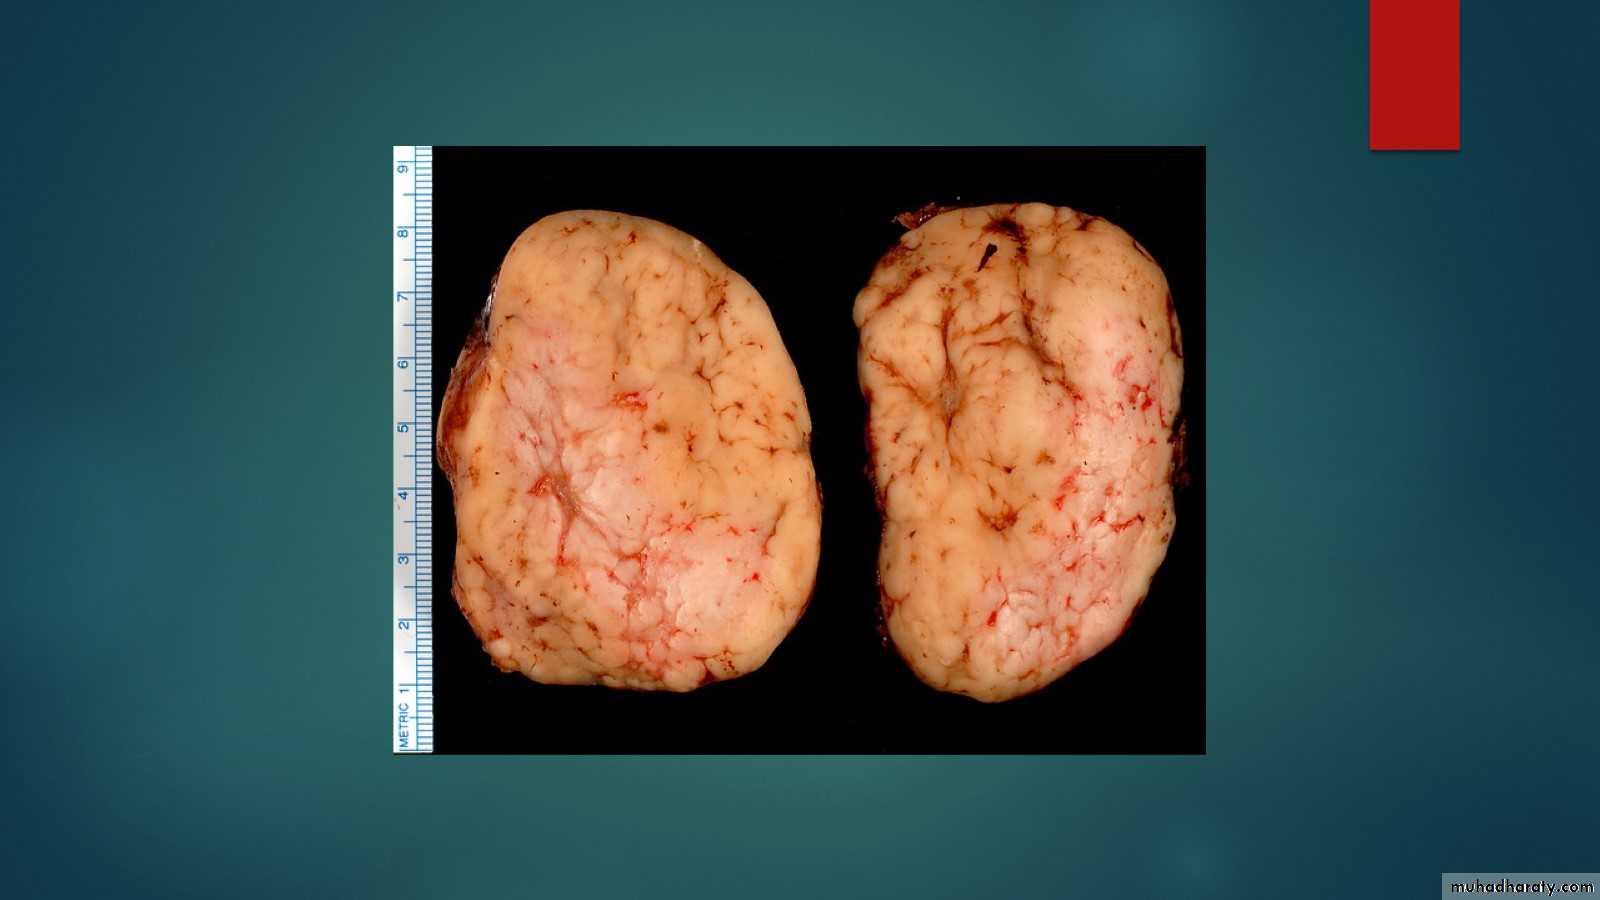

F. 41Y.CERVICAL LYMPHADEOPATHY AND SPLEENOMEGALY